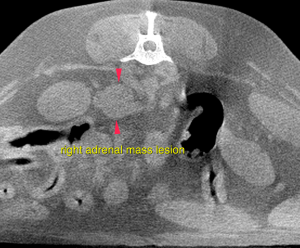

CT – Salivary gland, thyroid and right adrenal mass lesions, primary neoplasia, in a 12 year old MN Dachshund

The caudal pole of the right adrenal gland presents a nodular, moderately irregular contrast enhancing, mass lesion measuring 1.7 x 1.9 x 2.0 cm in size. A mass effect on the caudal vena cava is noted.

Salivary gland, thyroid and right adrenal mass lesions, primary neoplasia

Differential diagnosis for the salivary gland mass includes primary soft tissue neoplasia (fibrosarcoma) with invasion of the parotid salivary gland or – even though rare in canine – primary neoplasia of the parotid salivary gland (such as adenocarcinoma or less likely adenoma).For further workup – if not performed yet – FNA samples or biopsy are essential. Surgical excision is advised. The right thyroid gland presents a mass lesion compatible with primary neoplasia. Possible differential diagnosis are cystic adenocarcinoma or less likely adenoma. In dogs these are rarely functional. Surgical removal of the right thyroid is the therapy of choice. FNA samples from the right superficial cervical lymph node are essential prior to surgery for complete staging. The findings of the right adrenal gland are consistent with primary neoplasia. Possible differentials include functional/non-functional adenoma or adenocarcinoma, pheochromocytoma. Invasion of the phrenicoabdominal vein is likely, invasion of the caudal vena cava cannot be ruled out. The potential of vascular invasion increases the odds of a primary malignancy.